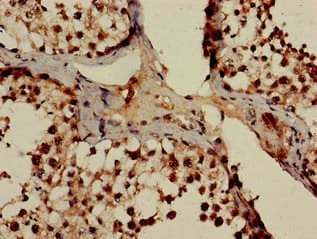

Rabbit Polyclonal POT1 antibody. Suitable for IHC-P, ICC/IF and reacts with Human samples. Immunogen corresponding to Recombinant Fragment Protein within Human Protection of telomeres protein 1 aa 250-450.

Applications ICC/IF, IHC-P